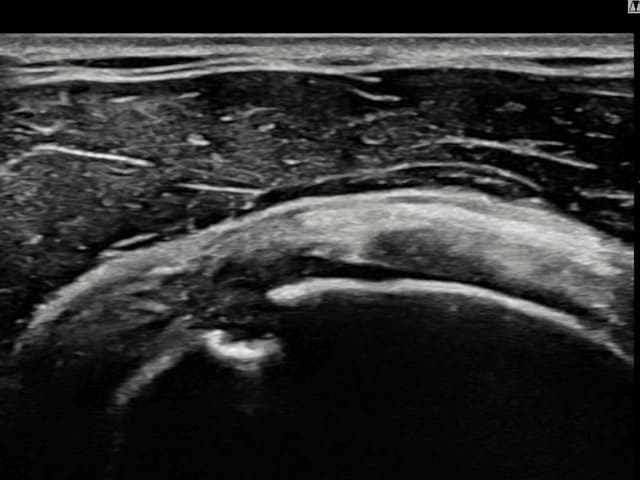

[촬영시기:22.09.19~22.12.09]

[어깨인대 축소봉합술] 우측 어깨 통증과 팔을 특정 각도로 올릴 때 심해지는 충돌 증상으로 내원하셨습니다.